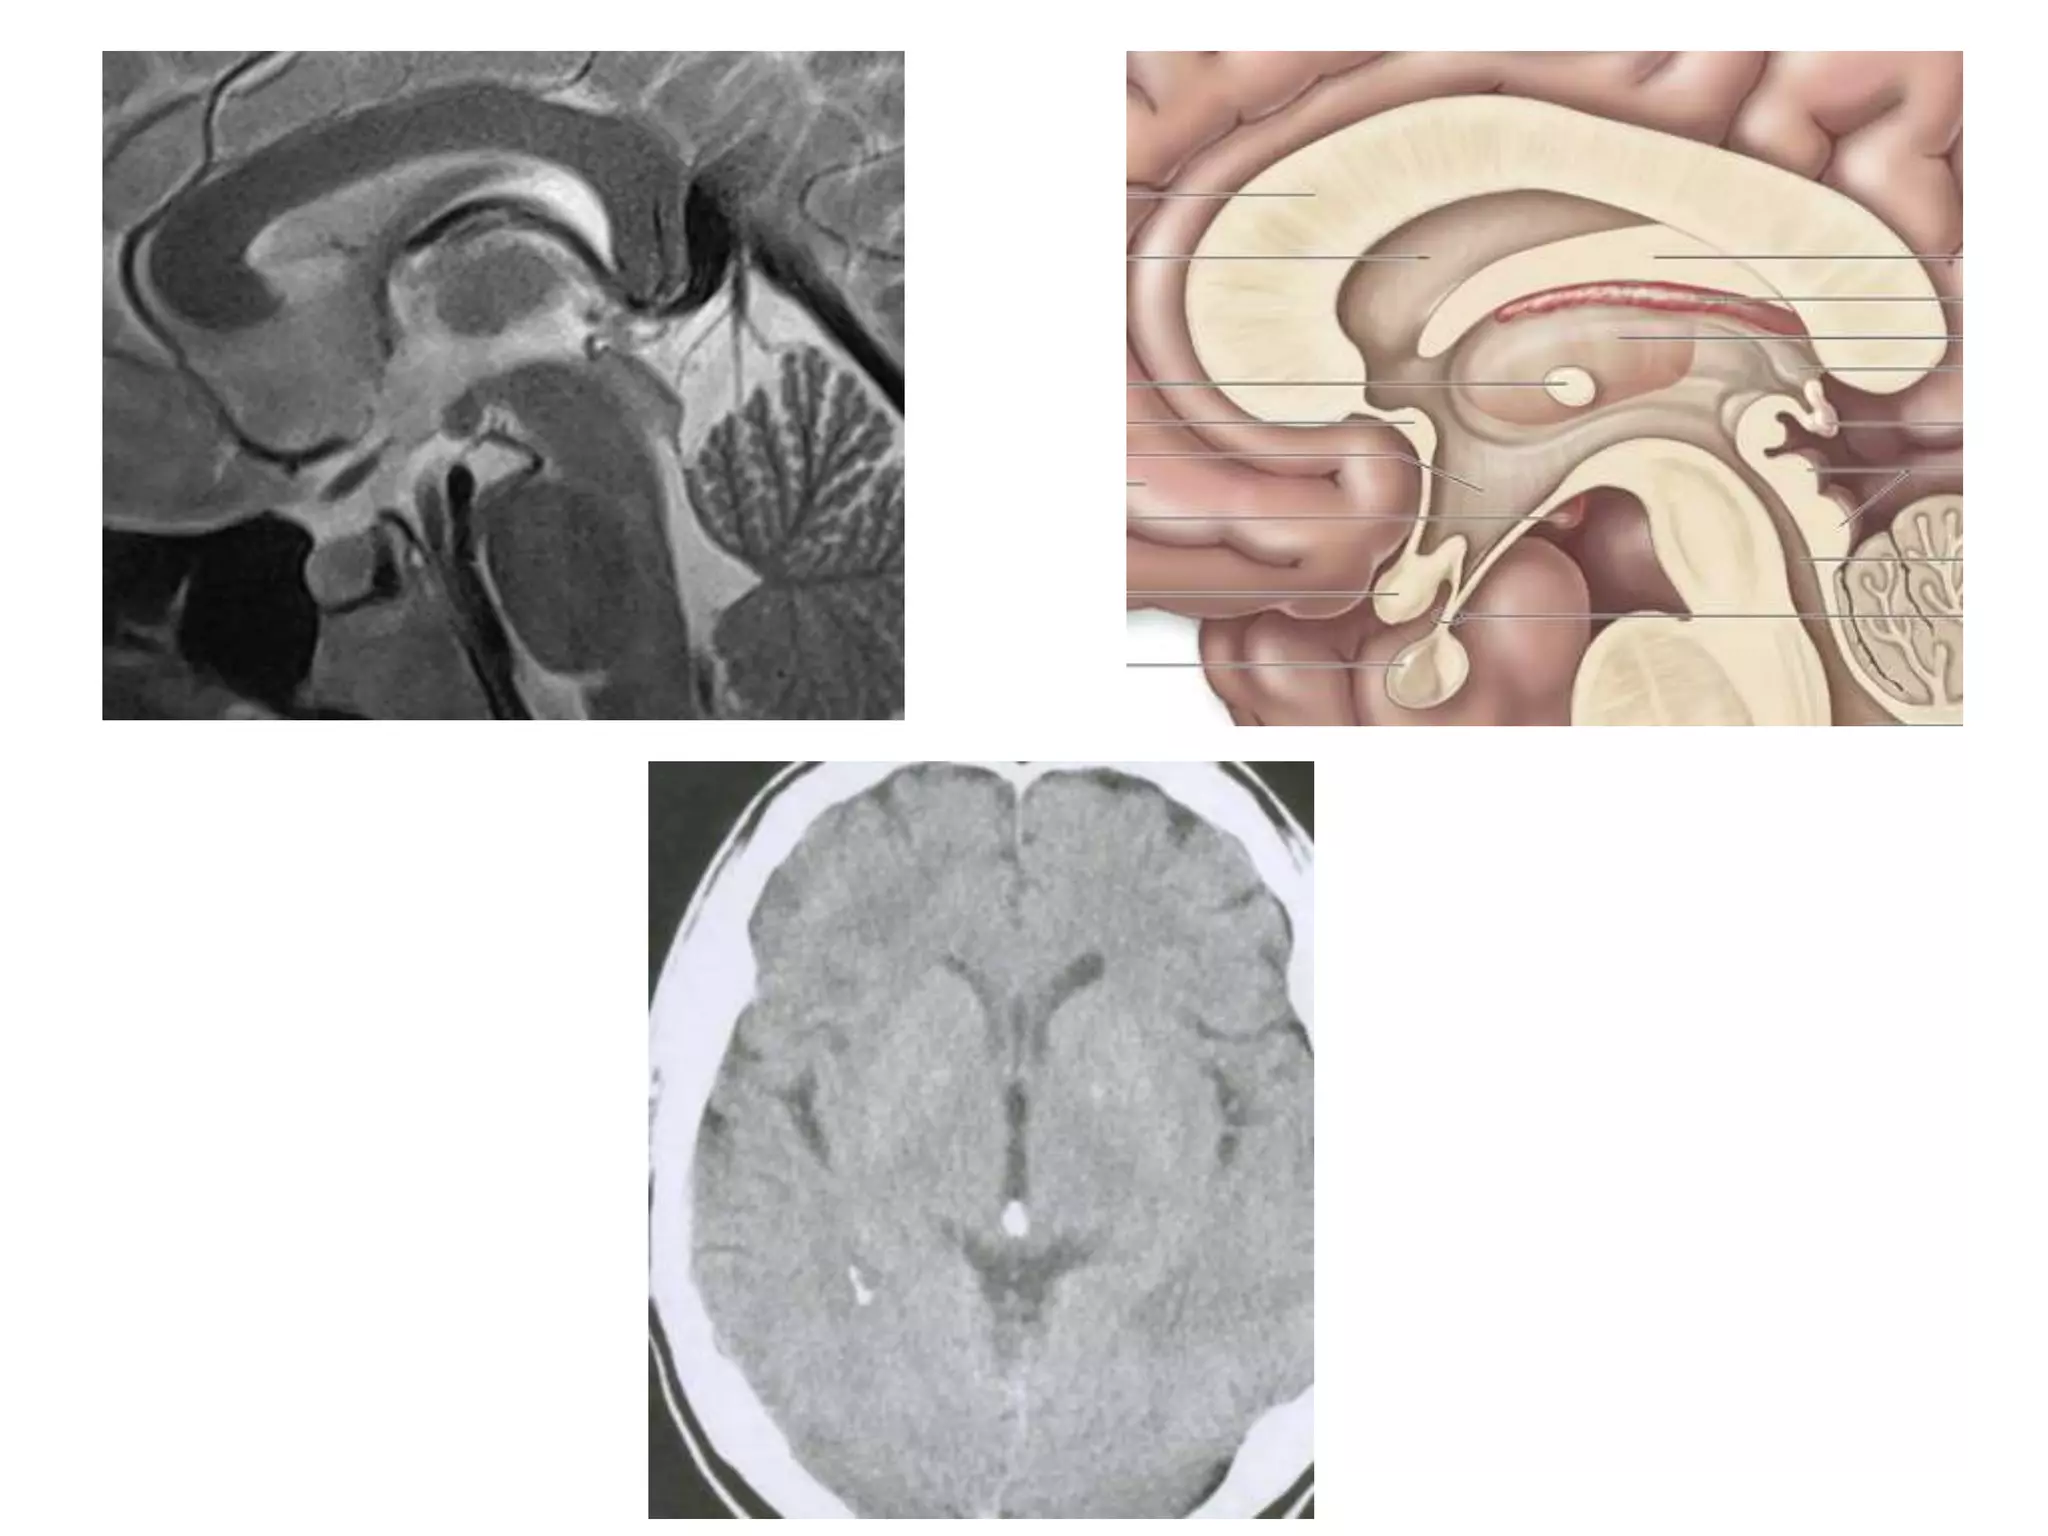

• Saggital and Coronal T1 weighted MRI – accurate

assessment of ventricles and C. callosum

• Mid Saggital section – for shape and configuration

of Aqueduct of Sylvius.

Saggital MRI : ‘C’ shaped , curving round the

thalamus.

• Radiology –

Axial MRI / CT - narrow cleft

Saggital MRI – elongated and complex curved shape

with upward, backward & downward arc.

Saggital MRI: concavity that curves downward

and forward towards the floor of 3rd ventricle.

Radiology

• Axial MRI / CT – ‘kidney bean’ turned on its side.

• Saggital MRI - mid point of line drawn b/w T. sella

and trocula should intersect middle of 4th

ventricle.

• Coronal MRI – elongated rhomboid shape